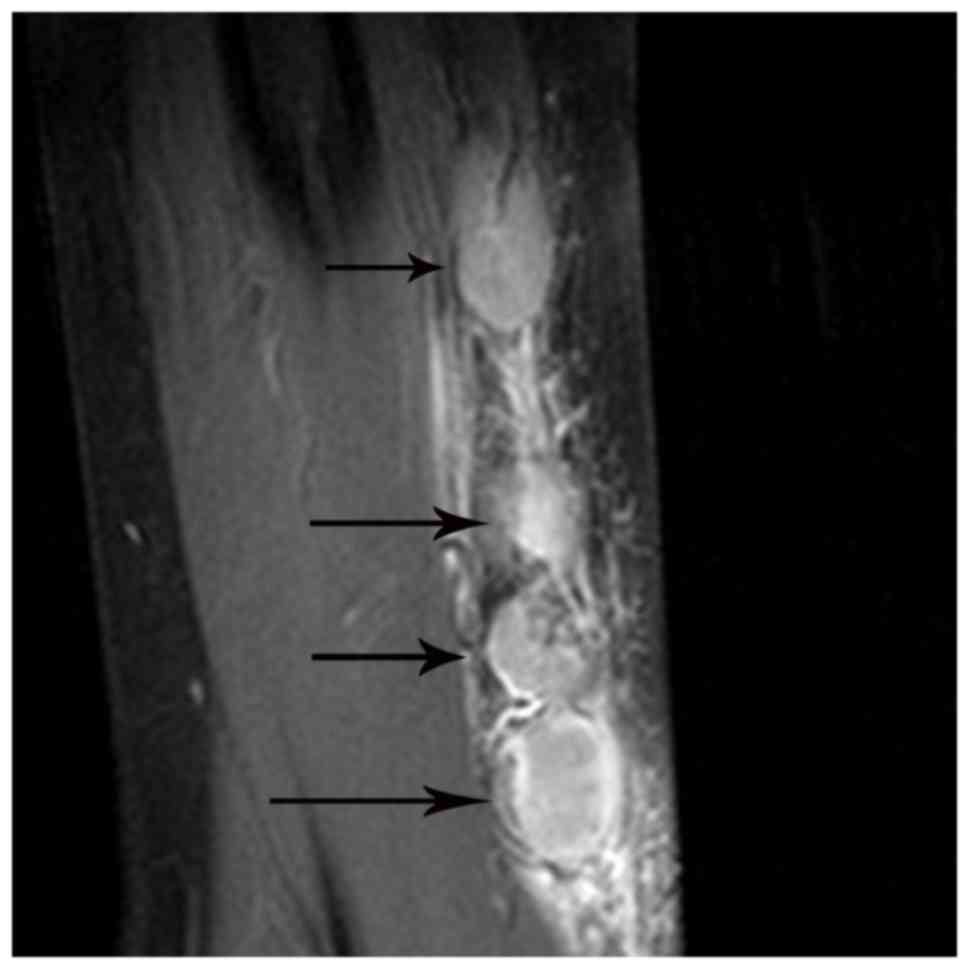

On the MRI scans, all the 14 nodes identified were homogeneously or heterogeneously isointense to muscle or with slightly increased intensity compared with that of muscle on T1WI, and homogeneously or heterogeneously hyperintense on fat-suppressed T2WI. Subsequent to enhancement, 8 of the 14 nodes displayed moderately homogeneous enhancement with no necrotic areas (Fig. 2) and 2 of the 14 nodes demonstrated marked heterogeneous enhancement with no enhancement of the necrotic central areas, which demonstrated patchy hypointense on T1WI and patchy hyperintense on T2WI in the center (Fig. 3A-C). Another 2 of the 14 nodes exhibited heterogeneous enhancement with marked enhancement of the astral hypointense area on T1WI and T2WI (Fig. 4A-C), and the other 2 exhibited heterogeneous enhancement with marginal petaloid enhancement of the astral hypointense area, namely the ‘rose flower’ sign (Fig. 5A-C). In addition, all 10 cases demonstrated general subcutaneous edema in the vicinity of the nodes.

Figure 2.

Multiple lymph node involvement in a 50-year-old man with cat-scratch disease at the early stage in the left elbow. The nodes (arrows) exhibit moderately homogeneous enhancement with no necrotic areas on an enhanced fat-suppressed sagittal T1-weighted imaging scan.